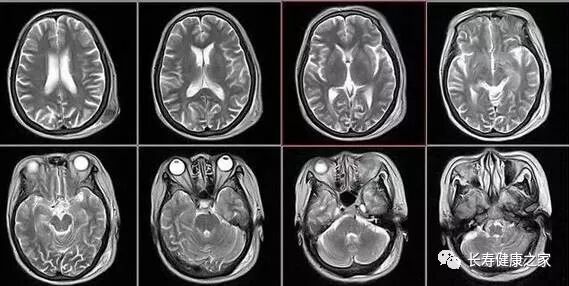

核磁共振

摇一摇再看

核磁共振机使用较强大的磁场,使人体中所有水分子磁场的磁力线方向一致,这时磁共振机的磁场突然消失,身体中水分子的磁力线方向,突然恢复到原来随意排列的状态。

简单说就相当于用手摇一摇,让水分子振动起来,再平静下来,感受一下里面的振动。所以,核磁共振(MRI)也被戏说为是摇摇看的检查。

颈椎腰椎

最佳选核磁、次选CT

颈椎病、腰椎间盘突出等椎间盘疾病需要观察椎间盘与相应的神经根,要想更好观察这些软组织,最优选择就是核磁。

同样,对于关节、肌肉、脂肪组织检查,核磁也是首选。